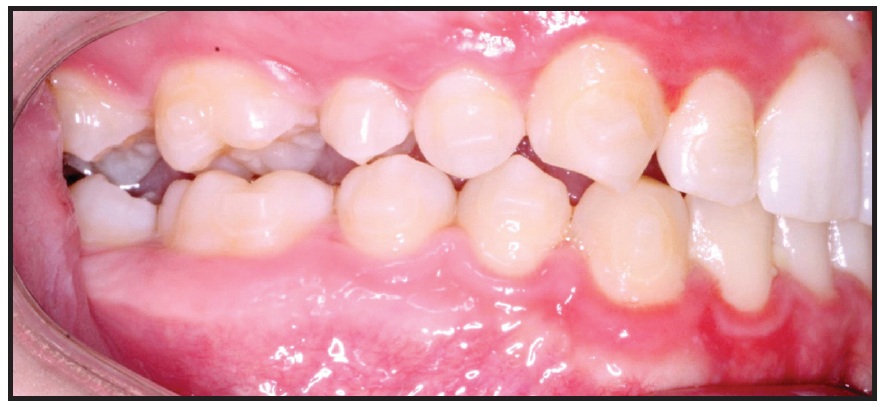

This example shows a 27-year-old female patient with a compensated Class II malocclusion (see attached video in the online version of this article). Note that the lower incisors are excessively proclined (IMPA of about 110°) in the pretreatment lateral cephalogram (Fig. 1).

Fig. 1 Patient with compensated Class II malocclusion (Class I dental, Class II skeletal) before treatment. Lateral cephalogram indicates proclined lower incisors, with IMPA of about 110°.